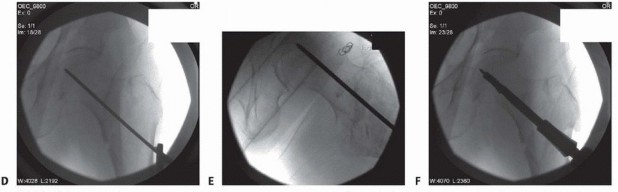

### TECH FIG 2 • Guide pin positioning and fracture preparation. A. Radiograph showing position of guide pin at the level of the lesser trochanter, just below the vastus ridge. B. Angled guide and guide pin inserted parallel to guide pin, showing femoral anteversion. C. Fluoroscopic image showing anteversion pin and inserted guide pin. - D. Guide pin advanced into center of the femoral head in the AP projection. E. Guide pin advanced into center of the femoral head in the lateral projection. Note the position of the post, which can be used as a reference in guiding the pin directly up the neck. In this case, the pin is lined up at approximately 90 degrees to the post or parallel to the floor. F. Triple reamer. The incision is carried through the fascia lata, posterior to the tensor muscle proximally. The vastus lateralis fascia and muscle is incised longitudinally 2 to 3 cm anterior to the linea aspera and retracted anteriorly. Care is taken to identify and control any perforating vessels supplying the vastus lateralis muscle. Proximally, the origin of the vastus lateralis is sharply released off the vastus ridge to allow atraumatic anterior retraction of the muscle to facilitate lateral femoral shaft exposure. Care should be taken to avoid any medial shaft dissection to maintain the vasculature to the fracture zone. ### Guide Pin Positioning for Sliding Hip Screw and Fracture Preparation The entrance point for the guide pin is selected once exposure of the lateral femoral cortex is completed. The entrance for a 135-degree plate is typically 2 cm below the vastus ridge, opposite the midpoint of the lesser trochanter, at the level of the femoral insertion of the gluteus maximus tendon ( TECH FIG 2). The entrance point for the guide pin is adjusted 1 cm proximal (for lower angled devices) or distal (for higher angled devices) from the 135-degree starting point for every 5-degree adjustment in the measured neck-shaft angle. The femoral anteversion can be estimated by advancing a free guide pin by hand up the anterior femoral neck and securing it in the anterior aspect of the femoral head. Alternatively, if a post is 408 used with the traction table, the angle of correct guide pin placement into the femoral neck may be determined radiographically based on the relationship of the femoral neck to the post. The angled guide is placed at the guide pin insertion site, centered in the AP plane on the femoral shaft and seated flush to the lateral cortex. It is preferred to use an angled guide rather than to place the guide pin freehand to avoid levering the side plate against the lateral cortex when compressing the side plate to the femur. The guide pin is advanced under fluoroscopic guidance, in both the AP and lateral views, to ensure central placement in the femoral head. If the guide pin is not centered in the head on both views, it must be removed and adjusted. The fracture reduction should be reassessed and the guide adjusted to ensure that central guide pin placement is obtained. The guide pin is inserted to within 5 mm of the joint line in both the AP and lateral projections. The intraosseous length of the guide pin is measured with the ruler provided in the instrument set. Care must be taken when deciding on a lag screw length, especially in highly unstable fractures reduced with a substantial amount of traction. Traction can cause fracture distraction and overestimation of lag screw length, which lead to screw prominence when traction is eventually released. The guide pin is then advanced into the subchondral bone to reduce the risk of inadvertent advancement or loss pin removal following reaming. A second guide pin can then be advanced into the femoral head proximal to the original guide pin to add stability in unstable fractures or in fractures that are reduced in anatomic alignment using excessive traction. This pinacts as a derotational pin to ensure that the proximal fragment does not rotate with reaming and screw insertion.